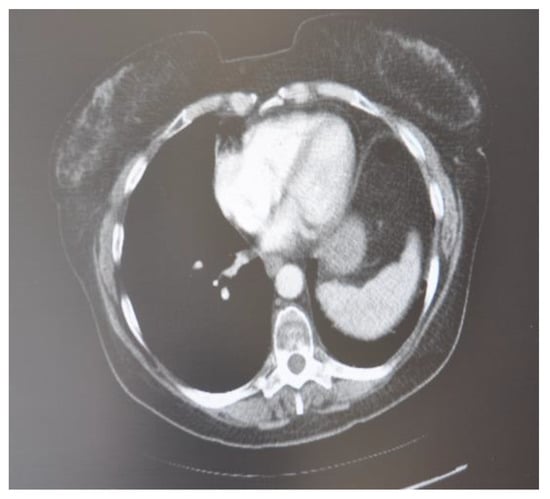

In October 2018, a 24-year-old patient arrived at our cryosurgery unit with the results of a CT scan. The presence of bilateral pulmonary and mediastinal lymph node metastases close to the esophagus was highlighted (Figure 6).

After cryotherapy and immunotherapy, very good postoperative evolution was noted, both radiological and analytical, and clinical (Figure 11).

In the follow-up checks that occur every 6 months for the first 3 years after cryosurgery and then every 12 months, no local or distant metastatic repetitions have been highlighted and the patient appears to be in an apparent state of good health.

Figure 6. CT scan images indicate the presence of bilateral pulmonary and mediastinal lymph node metastases close to the esophagus. The arrow indicates the tumor’s location.

Figure 11. CT scan images after cryotherapy in the patient with bilateral lung metastasis and mediastinal lymph nodes. The arrow indicates where the tumor was located.